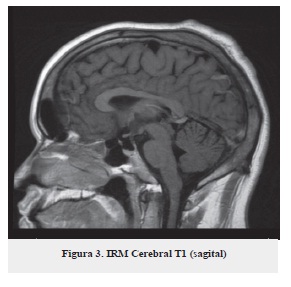

Se plantea como impresión diagnóstica: síndrome cerebeloso en estudio, por tal motivo se ordena resonancia magnética simple y con gadolinio (figuras 1, 2 y 3) no se observan lesiones ocupantes de espacio intra o extra axiales, no hay alteraciones de señal en el parénquima cerebral, cerebro medio o fosa posterior, no hay alteración en el cerebelo.